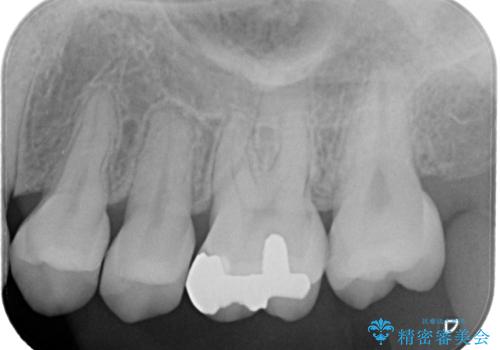

虫歯は小さい段階で見つけることが大切です。

早ければ早いほどいいですし、しっかりと型を取って治療することが今後のその歯を再治療しない為のポイントになってきます。